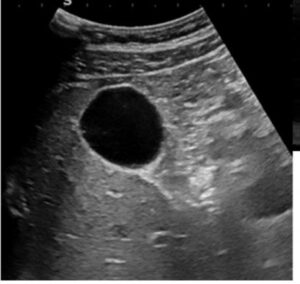

POCUS להערכת כיס מרה זו אחת הבדיקות הנפוצות ברפואה ראשונית (בקהילה ובבית החולים) במטופלים עם